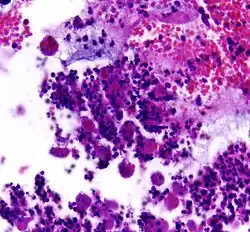

![]() | Diffuse B-cell lymphoma | Lymph node FNA specimen showing diffuse large B cell lymphoma. | Category: Histopathology of diffuse large B cell lymphoma | Diffuse large B-cell lymphoma |